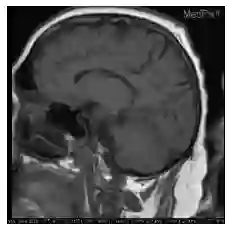

Understanding visual question answering is going to be crucial for numerous human activities. However, it presents major challenges at the heart of the artificial intelligence endeavor. This paper presents an update on the rapid advancements in visual question answering using images that have occurred in the last couple of years. Tremendous growth in research on improving visual question answering system architecture has been published recently, showing the importance of multimodal architectures. Several points on the benefits of visual question answering are mentioned in the review paper by Manmadhan et al. (2020), on which the present article builds, including subsequent updates in the field.

翻译:视觉问题解答对于许多人类活动至关重要,然而,它提出了人工智能工作的核心重大挑战。本文介绍了使用过去几年中出现的图像进行视觉问题解答的快速进展的最新情况。最近公布了改进视觉问题解答系统结构研究的显著增长,显示了多式联运结构的重要性。关于视觉问题解答的益处的若干要点在Manmadhan等人(2020年)的审查文件中有所提及,而本文章正是以该文件为基础编写的,包括随后在该领域进行更新。

视觉问答(Visual Question Answering,VQA),是一种涉及计算机视觉和自然语言处理的学习任务。这一任务的定义如下: A VQA system takes as input an image and a free-form, open-ended, natural-language question about the image and produces a natural-language answer as the output[1]。 翻译为中文:一个VQA系统以一张图片和一个关于这张图片形式自由、开放式的自然语言问题作为输入,以生成一条自然语言答案作为输出。简单来说,VQA就是给定的图片进行问答。